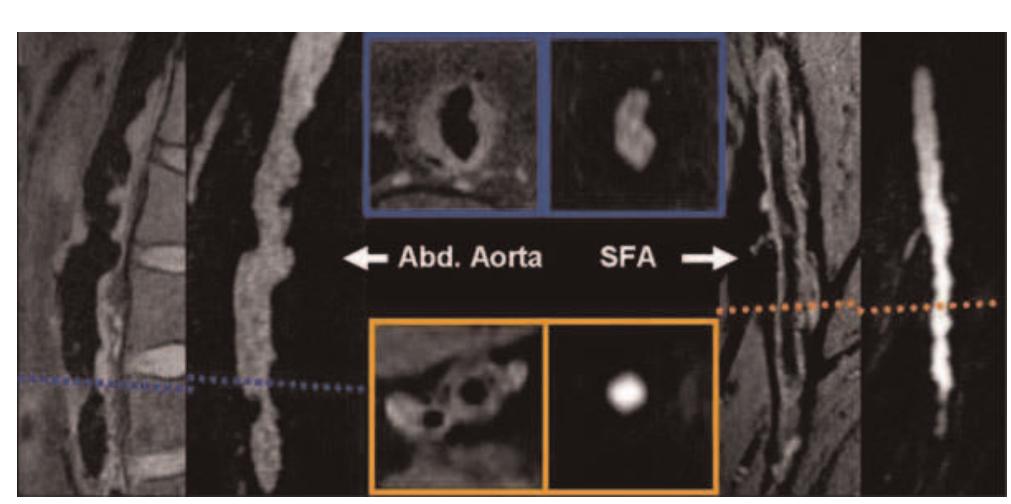

![Table | (abstract P24) Acquisition parameters for Tlw-SPACE and ce-MRA and bulk head motion during the long 3D acquisition time. Respiratory movement artefact is controversial [4], but Boussel [5] demonstrated its detrimental effect on carotid wall imaging, using real-time transaxial cines. However, during quiet supine respiration, breathing is predominantly diaphragmatic resulting in the greatest carotid movement in the head-foot direction. We used a novel high temporal resolution interleaved approach to study carotid artery movement in all directions, over the typical 3D scan duration, for a true representation of the potential problem for 3D imaging. Siemens, Erlangen) using two body matrix coils for the abdominal/pelvic area and a peripheral coil for thighs and lower legs. The imaging protocol included localizers, coronal acquisition of abdominal aorta and SFA using TIlw-SPACE, followed by ce-MRA covering the abdomen, thighs and the lower legs.](https://figures.academia-assets.com/44132452/table_029.jpg)